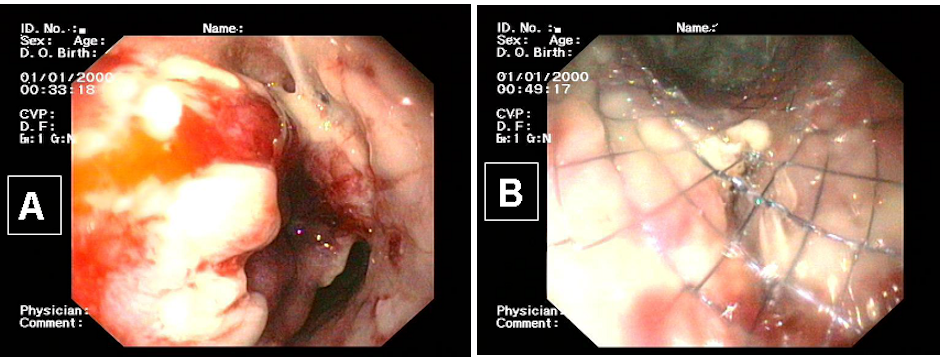

Die postoperative Phase nach Ösophaguseingriffen hat einen hohen Stellenwert. So muss der Patient sowohl klinisch als auch durch gezielte Diagnostik kontinuierlich überwacht werden. Komplikationen müssen zügig erkannt werden. Wenn sich Komplikationen abzeichnen, sollten schnelle diagnostische Maßnahmen folgen [45]. Diese können sich durch eine Qualitätsänderung des Drainagesekrets, Fieber, Unruhe des Patienten und Herzrhythmusstörungen bemerkbar machen [55]. Auch kann es zu laborchemischen Veränderungen mit Anstieg der Infektparameter kommen. Eine schnelle und gezielte Diagnostik insbesondere die Endoskopie (Abbildung 10A [Abb. 10]) und die Kontrastmittel-gestützte Spiral-Computertomographie können Komplikationen aufdecken und dadurch die Rate an Morbidität und Mortalität deutlich senken.

Abbildung 10: A: endoskopischer Nachweis einer Anastomoseninsuffizienz (Stern) bei Z.n. Magenhochzug und zervikale Anastomose. B: Stentimplantation zur Deckung der Anastomoseninsuffizienz.

Die Fortschritte in der Endoskopie haben die Versorgung einer Anastomoseninsuffizienz deutlich erleichtert. Durch endoskopische Stentplatzierung bei Anastomoseninsuffizienz wird in den meisten Fällen ein schneller und suffizienter Defektverschluss erreicht [29], [56], [57] (Abbildung 10B [Abb. 10]). Auf komplexe Reoperationen kann durch diese Maßnahme in den meisten Fällen verzichtet werden [58]. Allerdings ist bei Nekrosen des Ersatzorgans ein operatives Vorgehen weiterhin unumgänglich. Auch Komplikationen wie Ösophagotrachealefistel oder postoperative Tracheanekrose (meist Pars membranacea), insbesondere bei Patienten mit Zustand nach neoadjuvanter Therapie, erfordern eine chirurgische Revision mit komplizierten Rekonstruktionseingriffen [59]. Abbildung 11 [Abb. 11] zeigt einen Trachealdefekt nach Ösophagektomie und Magenhochzug. Die Defektdeckung wurde durch ein Perikardpatch und Interposition eines M. Latissimus dorsi Schwenklappens erreicht.